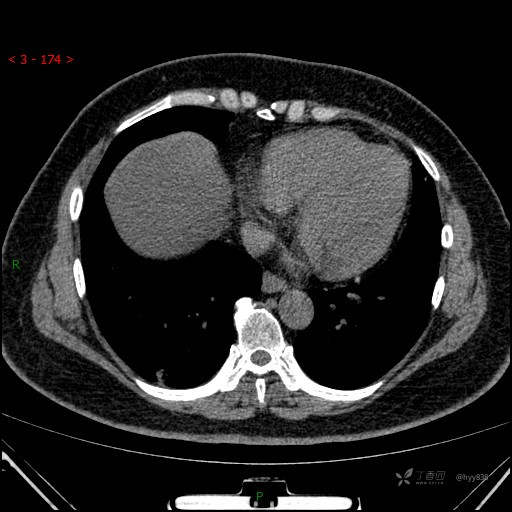

胸部CT平扫